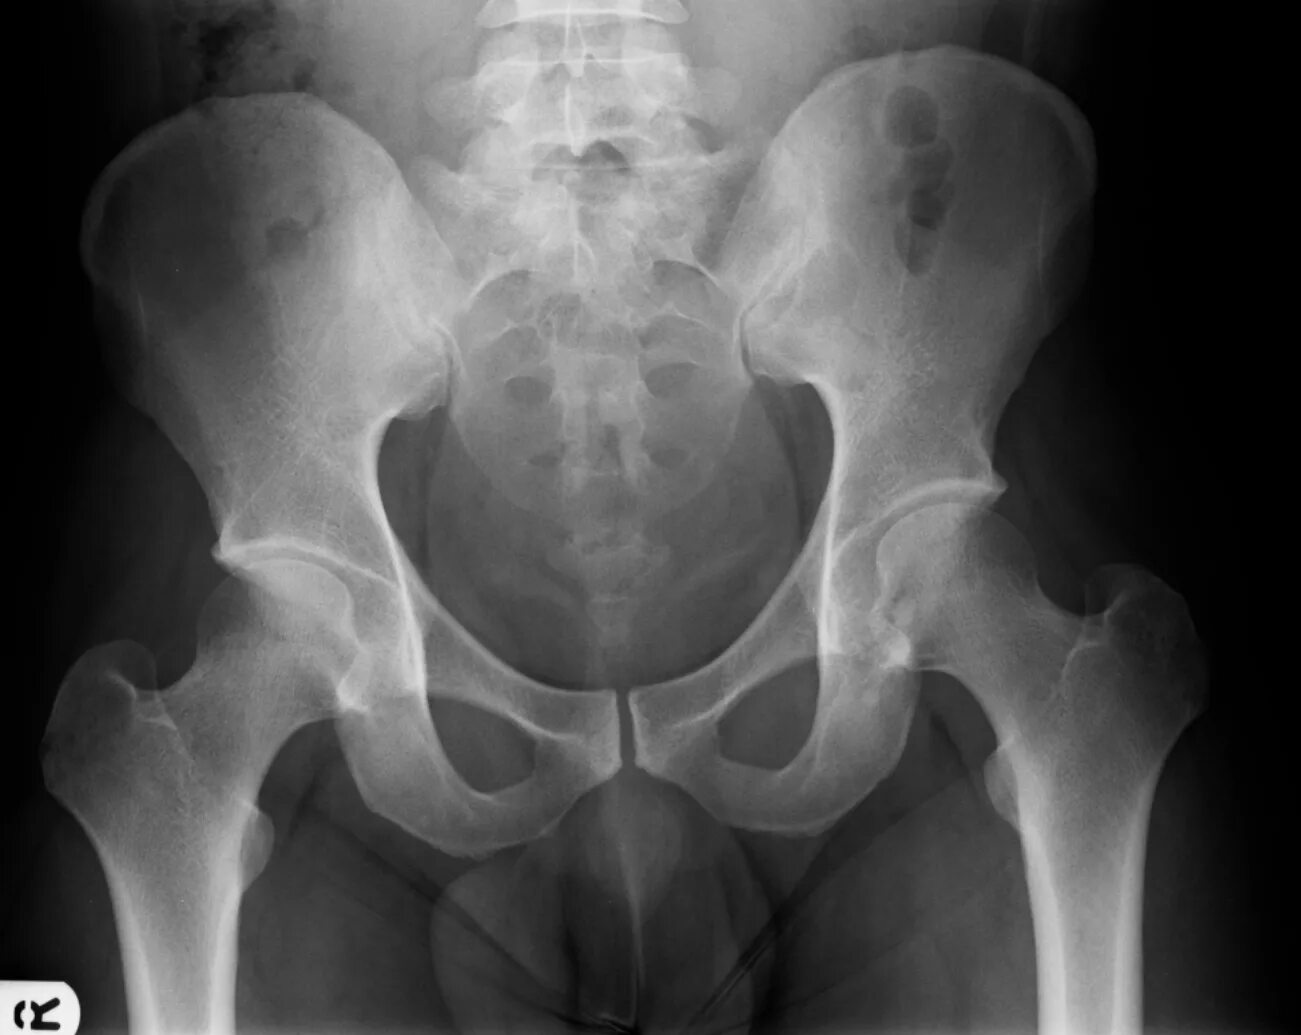

Боли в симфизе